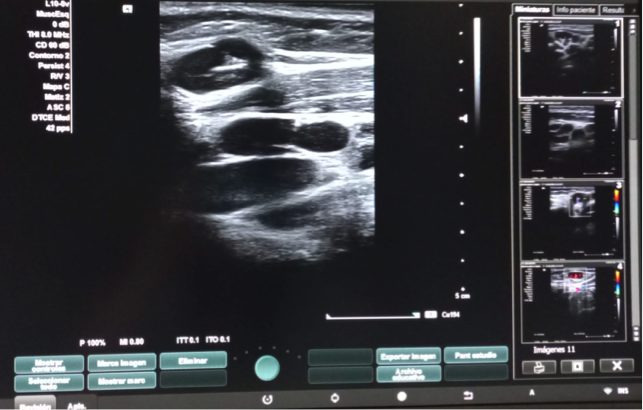

Hallazgos ecográficos

Dos adenopatías en territorio laterocervical derecho, con hilio central y doppler positivo, alguna con diámetro transversal superior al longitudinal, de probable origen reactivo y una adenopatía supraclavicular sin hilio central y con vascularización generalizada.